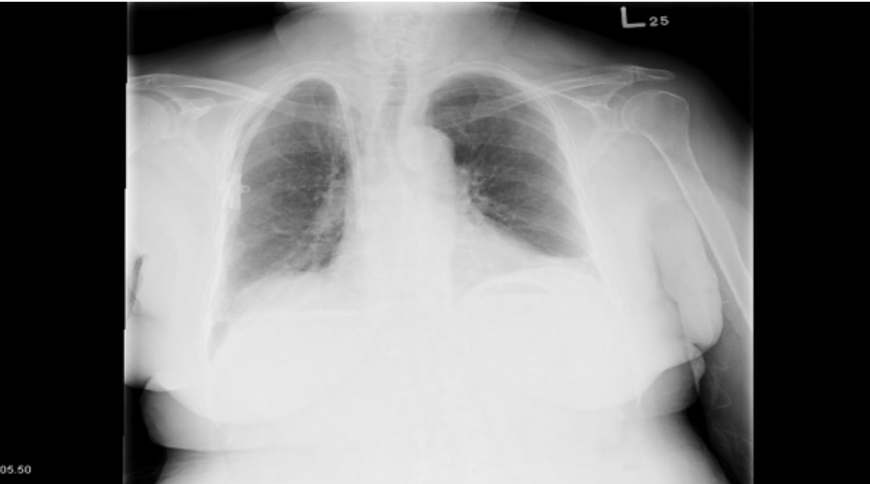

半年後の定期健診(2006年6月)で腫瘍マーカーのCEAが断続的に上昇していたので、レントゲンを撮影した結果、肺癌と診断された。

肺癌と診断された後、2006年7月に緊急手術が行われ、胸を開いてみると、レントゲンで見つかった2センチメートルの2個の腫瘍のほかに、左肺葉と胸膜に転移が見つかり、なすすべがありませんでした。

T様はアントロキノノール含有エキスを服用し続け、毎月定期健診をしていたところ、病状は改善されていきました。そして一年後の2009年7月24日の各種検査でがん細胞は検出されなくなり、他の検査の数値も安定していました。